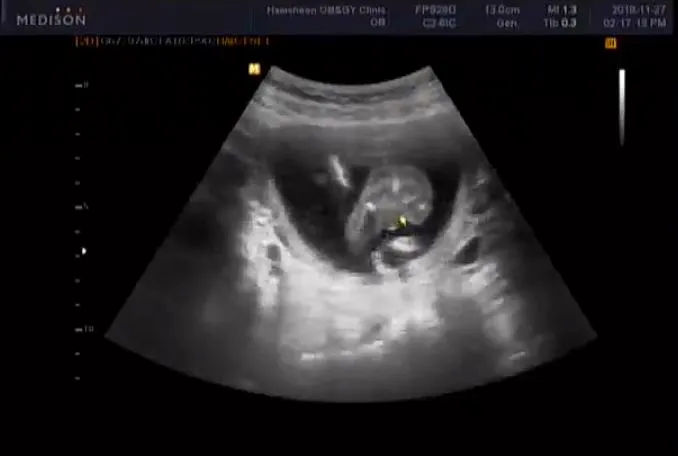

짠짠이 16주 차

16주.

점점 아기의 형태를 갖춰가는 짠짠이. 몸길이는 자기 주수와 비슷한데 머리는 1주 정도 더 크다(...). 표준 성장 주수가 서양 아기에 맞춰져 있어서 동양 아기는 몸이 짧고 머리가 더 크게 나오는 게 일반적이라고. 그게 무슨 상관이랴 건강하게만 자라면 되지 라고 생각은 했지만 그래도 짠짠이만 머리가 큰 게 아니라니 마음이 살짝 놓이는 게 솔직한 심정. 하지만 아빠가 머리가 크니 아마 마찬가지일 거야 짠짠아 미안. 그나저나 짠짠이 이 자식 다리 사이에 뭔가 있구나?!